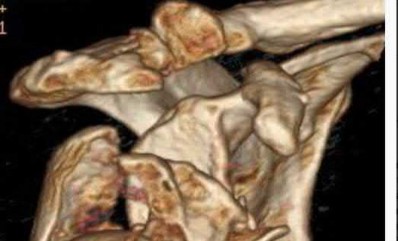

A 22-year-old male falls onto an outstretched hand and sustains a displaced fracture through the proximal pole of the scaphoid. Avascular necrosis of the proximal pole is highly likely due to the disruption of its primary vascular supply. Which vessel provides this critical retrograde perfusion?

Correct Answer: Dorsal carpal branch of the radial artery

The primary blood supply to the scaphoid is from the dorsal carpal branch of the radial artery, which enters the dorsal ridge of the scaphoid at the waist and courses proximally. This retrograde blood flow makes proximal pole fractures highly susceptible to avascular necrosis and nonunion. The superficial palmar branch provides a minor supply (about 20%) to the distal pole.